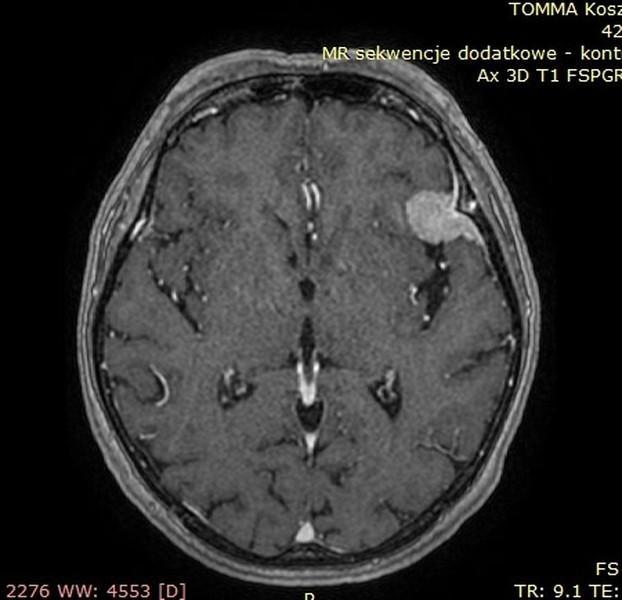

OPONIAKI DUŻYCH ROZMIARÓW I OPONIAKI OLBRZYMIE

Od wielu lat zajmuję się chirurgią oponiaków wewnątrzczaszkowych o różnych lokalizacjach oraz rozmiarach. W grupie operowanych przypadków znalazły się także oponiaki dużych rozmiarów i oponiaki olbrzymie. Guzy te potrafią rosnąć powoli. Wielokrotnie objawy kliniczne przez wiele lat są niespecyficzne - tylko bóle głowy!!! Początkiem przyspieszonej diagnostyki bywa pierwszy w życiu napad padaczkowy. Tak było w grupie prezentowanych przypadków dużych/olbrzymich oponiaków. Wiele z tych guzów pomimo swojej naturalnej łagodności stanowi poważne wyzwanie operacyjne. Operacja oponiaka – to działanie operacyjne wobec guza rosnącego zewnątrzmózgowo, wielogodzinne spokojne oddzielanie i usuwanie „żeby mózg o tym nie wiedział”

Poniżej przedstawiono grupę operowanych pacjentów.

Pacjent pierwszy - Guz usunięty całkowicie, guz łagodny. Pacjent w stanie dobrym, bez objawów neurologicznych – wypisany do domu.

Przed operacją

Tak jak napisałem guzy - oponiaki potrafią rosnąć powoli nie dając żadnych objawów, mózg dostosowuje się do utraty rezerwy wewnątrzczaszkowej dlatego, że proces przebiega powoli. Początkowym objawem był pierwszy w życiu napad padaczkowy. Potem diagnostyka – rezonans magnetyczny i operacja oponiaka. Działanie operacyjne wobec guza rosnącego zewnątrzmózgowo, wielogodzinne spokojne oddzielanie i usuwanie „żeby mózg o tym nie wiedział”

Poniżej prezentacja badan diagnostycznych:

• Ryc 1-7 – badania diagnostyczne przedoperacyjne,

• Ryc 8-13 – badania po operacji.

Pacjentka przyjęta nieprzytomna po napadzie padaczkowym – podczas operacji guz został usunięty całkowicie, miał charakter łagodny. Pacjentka w stanie dobrym, bez objawów neurologicznych – wypisana do domu.